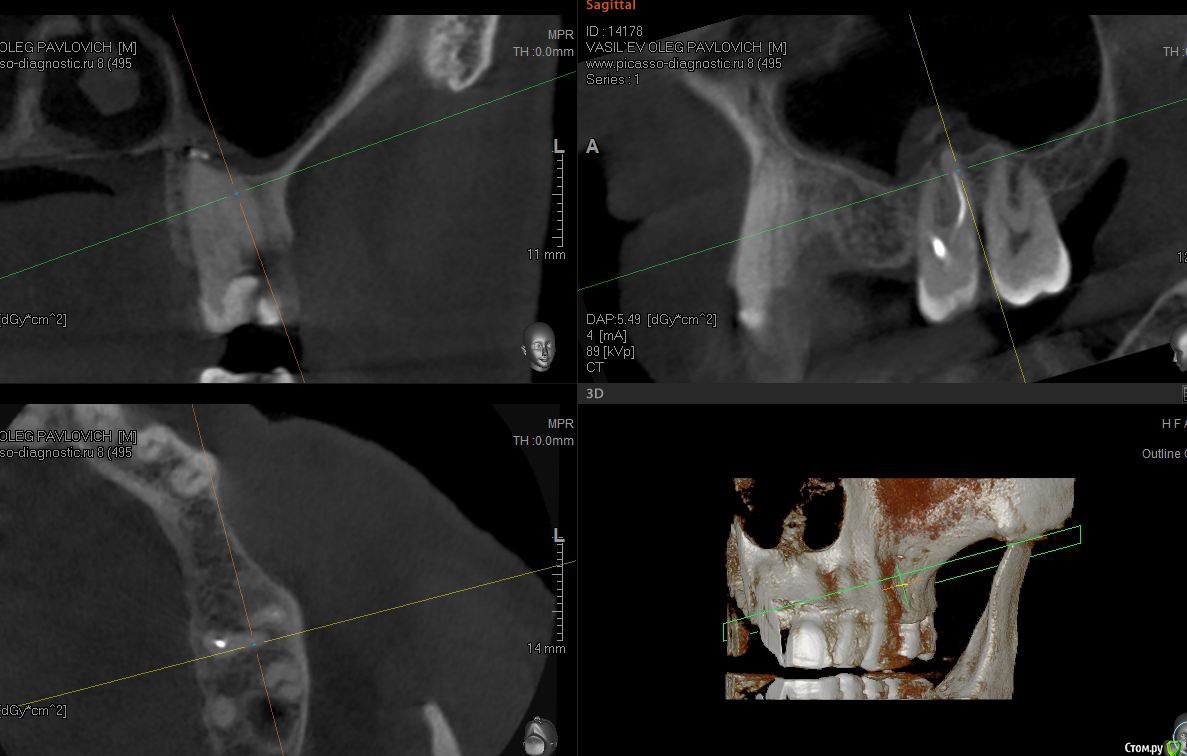

sugaka30 Опубликовано 7 января, 2017 Автор Поделиться Опубликовано 7 января, 2017 (изменено) Сделал Кт Может кто прокоментирует Не пора ли мне Пора? А то что то мне все плохеет https://yadi.sk/d/RXxAPdk237XVpi Заранее спасибо Изменено 7 января, 2017 пользователем sugaka30 Ссылка на комментарий

sugaka30 Опубликовано 7 января, 2017 Автор Поделиться Опубликовано 7 января, 2017 И скажите все таки есть перфо материала в гайморову или пронесло? Ссылка на комментарий

sugaka30 Опубликовано 22 января, 2017 Автор Поделиться Опубликовано 22 января, 2017 Проконсультируйте пожалуйста по этим срезам А то местный хирург не может понять что не так Ссылка на комментарий

St. Опубликовано 22 января, 2017 Поделиться Опубликовано 22 января, 2017 Скрины кт в обл леченного зуба Ссылка на комментарий